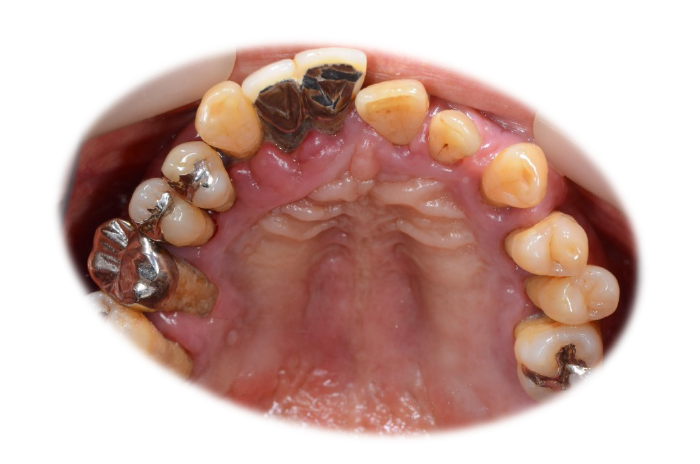

初診時の状態

歯周病により歯はグラグラの状態で、元の位置から動いてしまっていました。

また、レントゲン写真でも歯を支えている骨が吸収していることが明らかで、噛む力を十分に支えられない状態でした。

このままの状態で歯を残すことは難しく、抜歯が必要と判断しました。

初診時口腔内写真